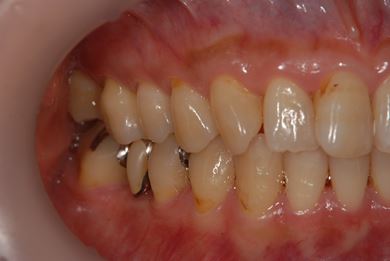

インプラントの症例写真 IMPLANT

インプラント治療

| 性別/年齢 | 女性 / 46歳 | ||||||||||||||||||||||||||||||||

| 主訴 | 左奥歯のインプラント治療を希望。 | ||||||||||||||||||||||||||||||||

| 治療方針 | 左下奥、欠損部分をインプラント治療にて、機能的・審美的回復を行う。 | ||||||||||||||||||||||||||||||||

| 治療内容 | インプラント2本、ハイブリッドセラミッククラウン2本 | ||||||||||||||||||||||||||||||||

| 総治療費 | 399,000円 | ||||||||||||||||||||||||||||||||

| 治療期間 | 5ヶ月 |